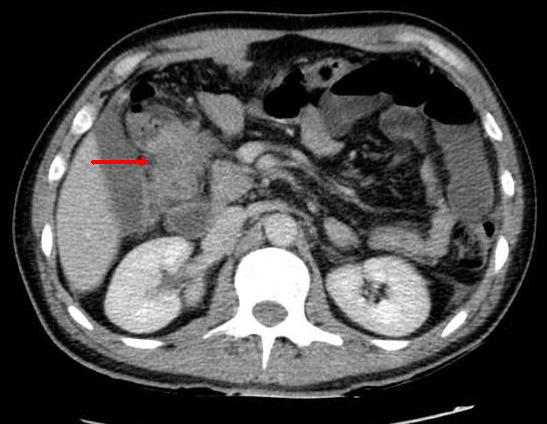

Image de l'occlusion du colon

Le colon est tres distendue a diametre depasse 6cm ,

sa paroi est epaisse que du grele et les plies de

haustral est intercale . Image TDM en coupe coronale |

|

Meme cas en coupe axilae .

L'intestin est normale ( valvule de Bauhin est

normale ) |